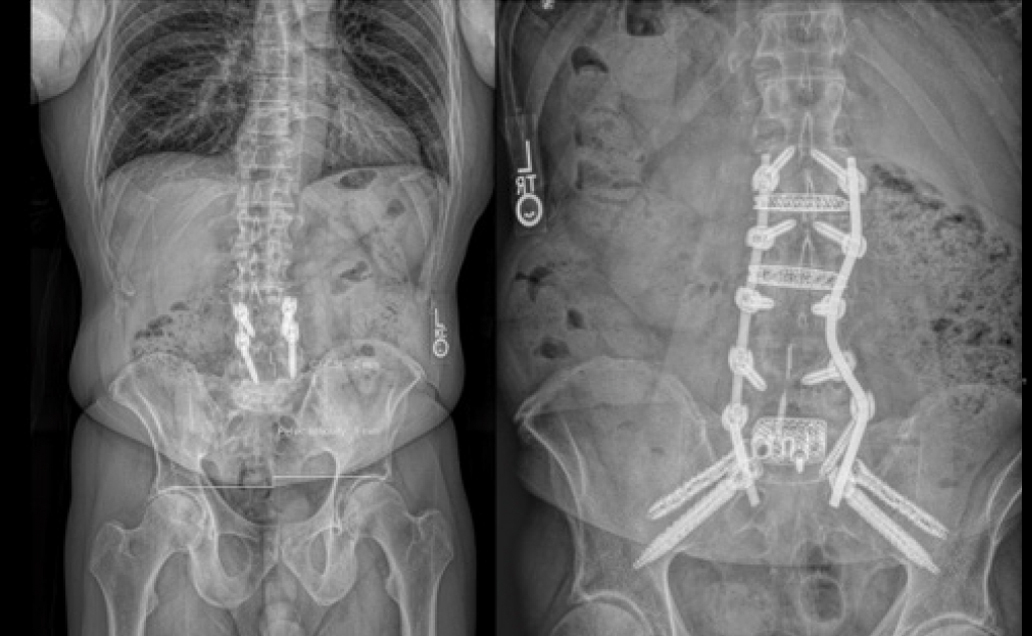

Surgical Treatment:

- ALIF L5-S1 with LLIF L2-4 in single lateral position

- L2-pelvis fusion with MIS S2AI iFuse Bedrock Granite™ and iFuse TORQ™ for bilateral SAI spinopelvic stabilization and SI joint fusion

Post-op:1,2

- Marked pain relief and normalized posture at 6-month post-op

- Walking 4-5 miles

- Anxious to return to pickle ball

Inline eastlack case 2 03

Inline eastlack case 2 04